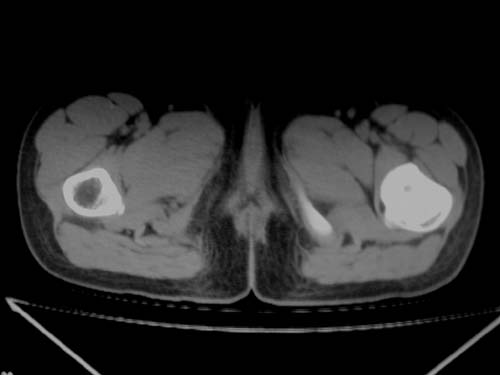

标题: CT19608:女12岁,左髋部疼痛,无发热病史 [打印本页]

标题: CT19608:女12岁,左髋部疼痛,无发热病史

左股骨干增粗,磨玻璃样改变——考虑骨纤维异常增殖症!

考虑左股骨上段骨纤维异常增殖症。

左股骨干增粗,磨玻璃样改变——考虑骨纤维异常增殖症!骨化性纤维瘤?